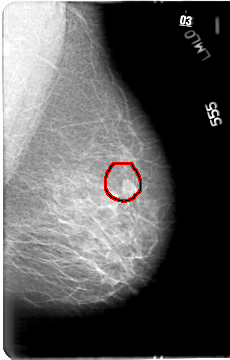

D_4033_1.LEFT_MLO

FILE: D_4033_1.LEFT_MLO.OVERLAY

TOTAL_ABNORMALITIES 1

ABNORMALITY 1

LESION_TYPE MASS SHAPE IRREGULAR MARGINS ILL_DEFINED

ASSESSMENT 0

SUBTLETY 5

PATHOLOGY BENIGN

TOTAL_OUTLINES 1

BOUNDARY